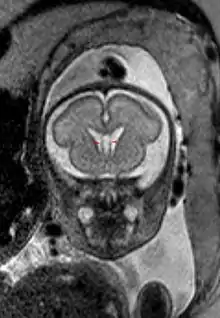

Полость прозрачной перегородки (лат. cavum septi pellucidi) — полость, находящаяся между листками прозрачной перегородки. Полость содержит ликвор, попадающий туда через поры в листках.[1]

Размер полости крайне вариабелен, у некоторых полость полностью закрыта, в то время как у других отмечается практически полное её незаращение (до 46 мм в корональной плоскости).[3]

Собственно полость прозрачной перегородки расположена на уровне основания передних рогов боковых желудочков мозга, а её распространение в заднем направлении в область тел боковых желудочков выделяют под названием полость Верге (лат. cavum vergae). Во время эмбрионального развития происходит закрытие полостей в задне-переднем направлении, из-за чего персистирование полости Верге при закрытой полости прозрачной перегородки встречается значительно реже.

Полость прозрачной перегородки существует у 100 % эмбрионов человека, однако более чем в 85 % случаев она закрывается к возрасту 3-6 месяцев.[4][5]